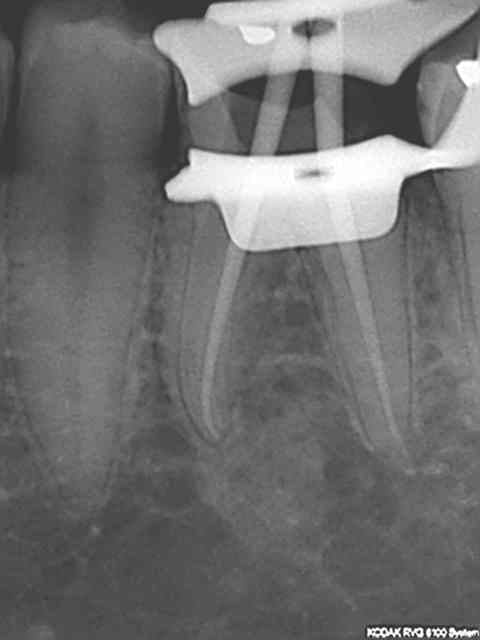

+1 l'interet c'est de faire partager ses astuces. Je ne prétend pas etre le roi de l'endo mais en ce qui me concerne j'ai trouvé une séquence qui me permet d'avoir des résultats reproductibles en un minimum de temps. Une autre 40 mn.

avec quelle technique d'obturation obtiens tu de si belles images radio?

La plus simple lentulo scellement monocone, tuck back à l'apex quand même.